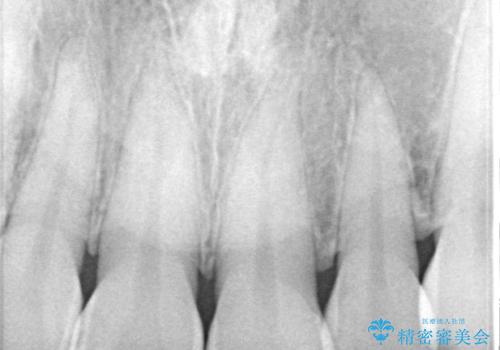

- 以前保険診療で行った前歯を自然できれいなセラミックにしたいと来院された患者様です。

古い材料と虫歯を除去して、土台の形を整え、より自然なオールセラミッククラウンにすることとしました。